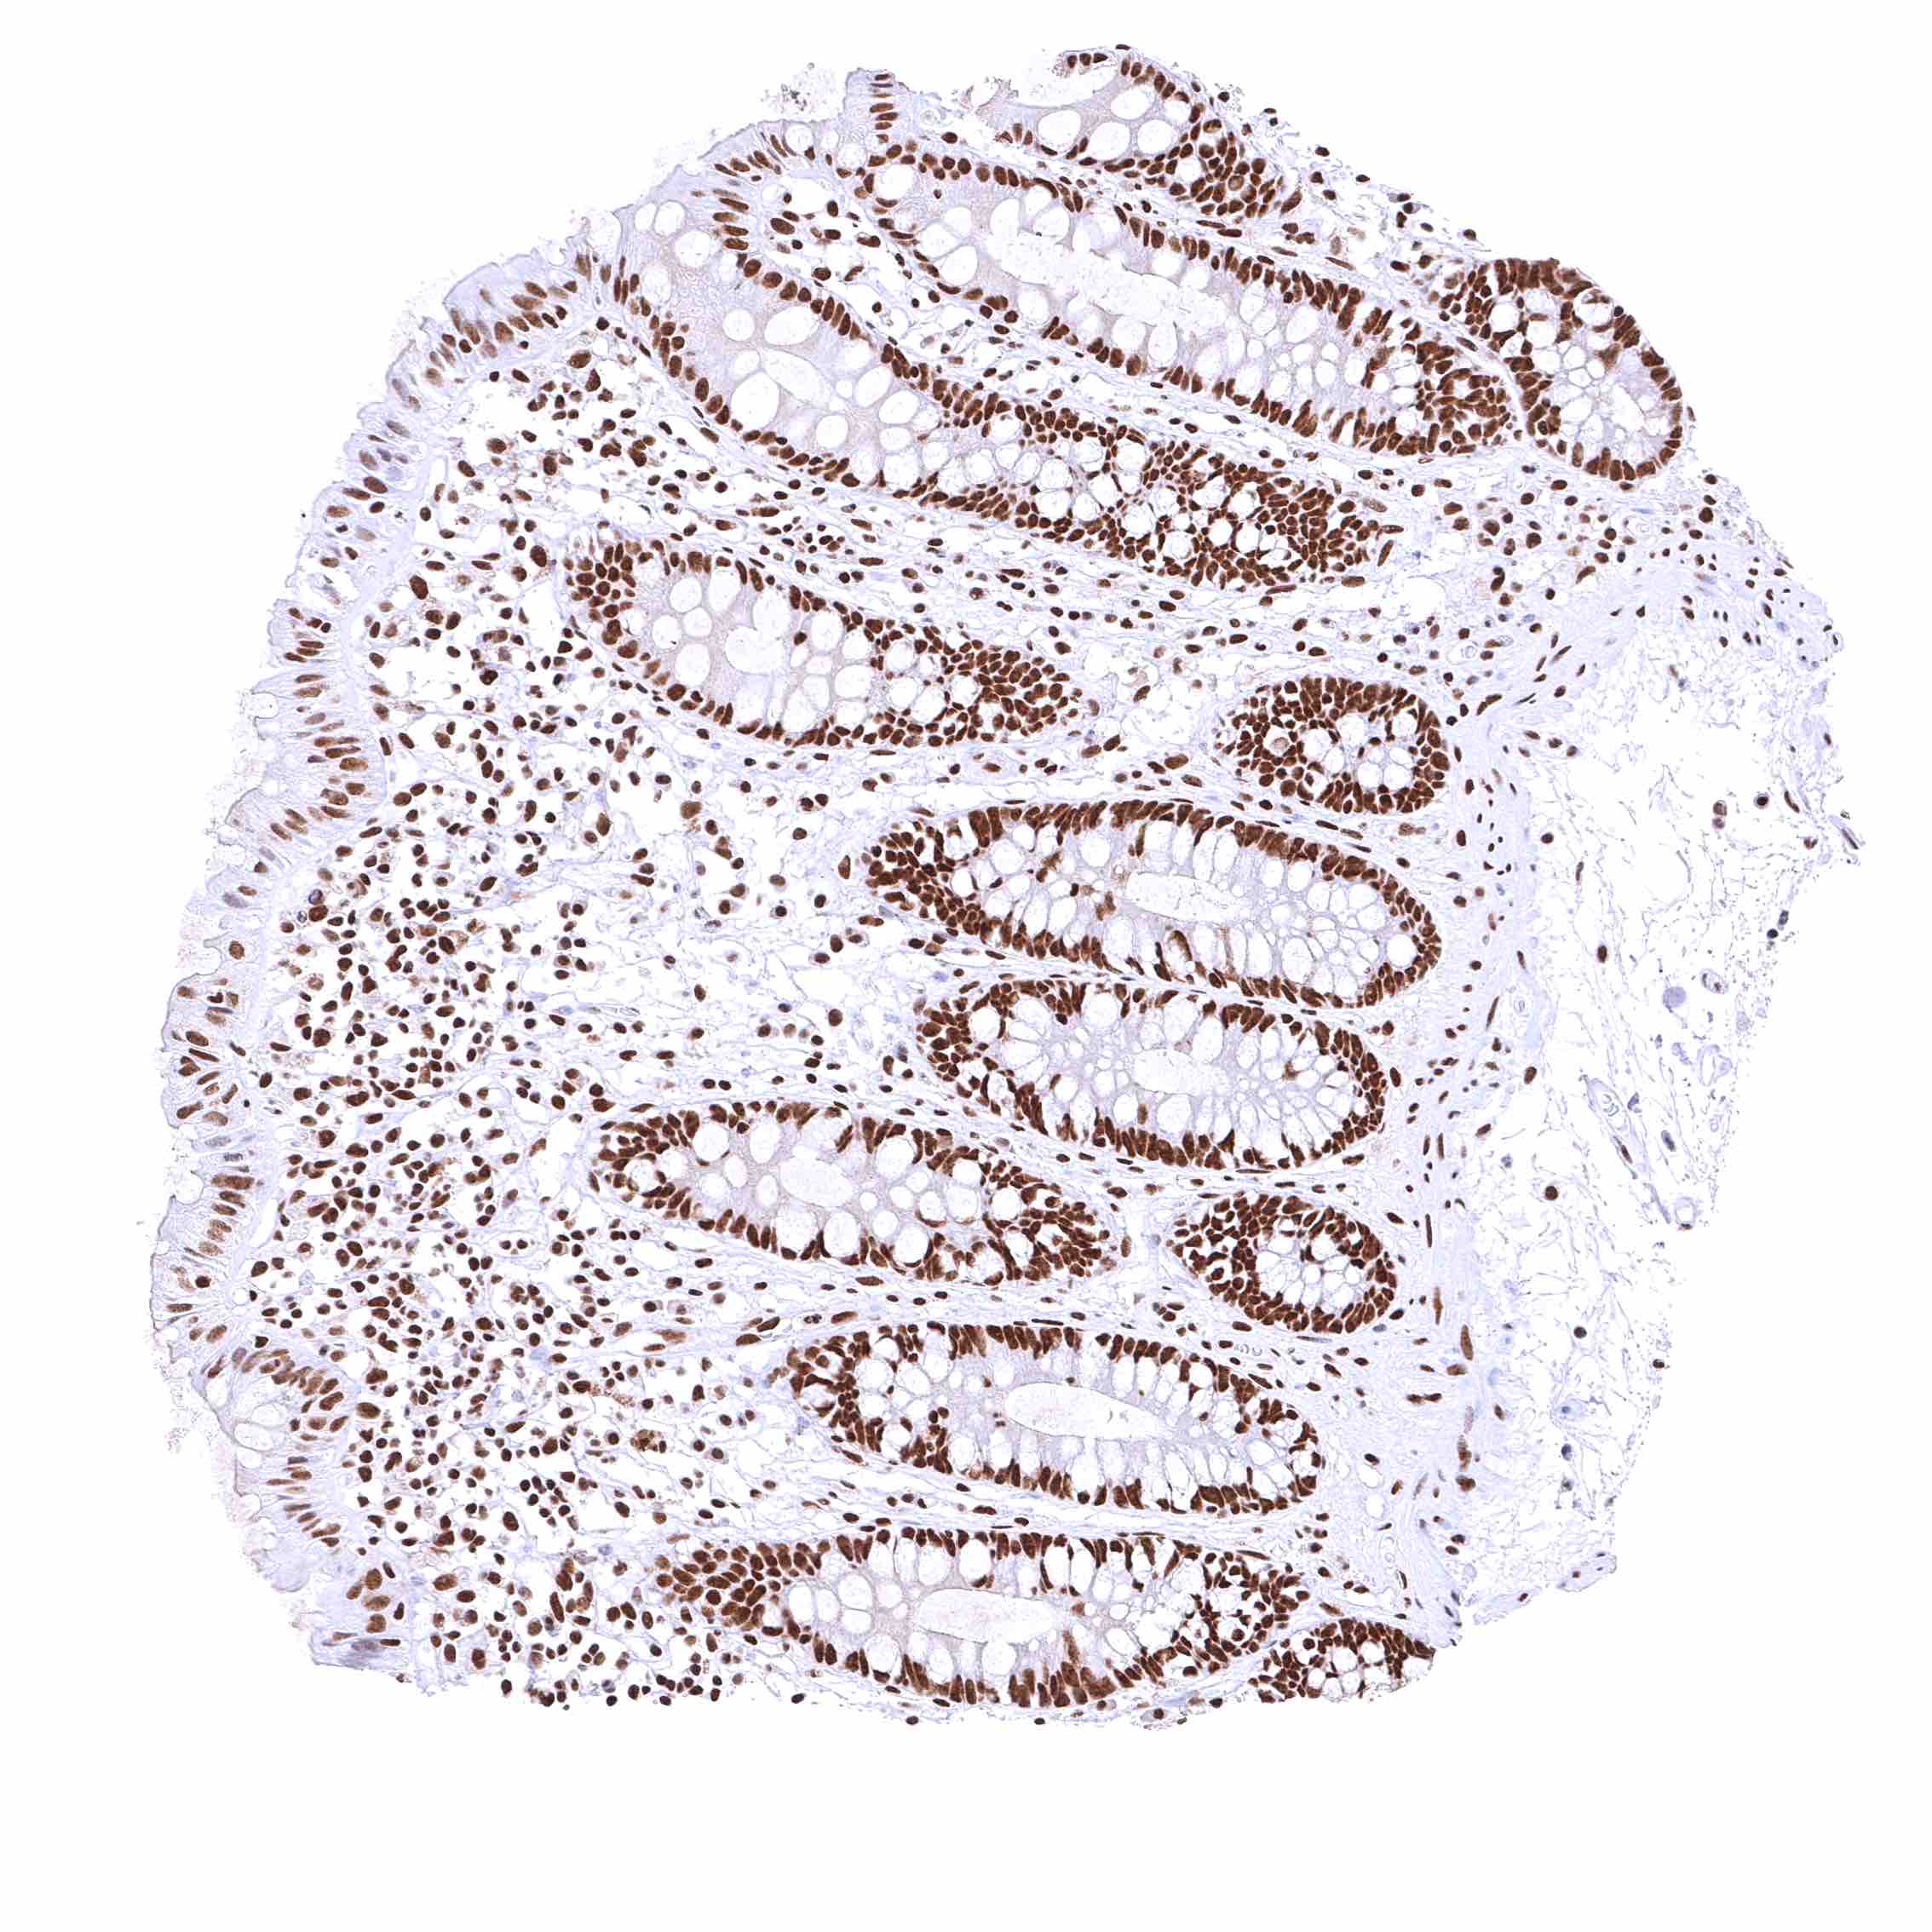

Colon descendens, mucosa – Nuclear BRD4 staining of surface epithelial cells is weaker than in crypts.